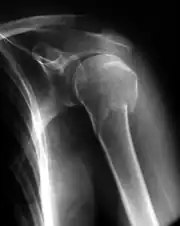

Fractura del húmero

La fractura del húmero se observa en todos los grupos de edad, pero es más frecuente en los ancianos y adultos jóvenes.[1] Se puede clasificar por la ubicación del húmero implicada: el extremo superior, el eje, o el extremo inferior.